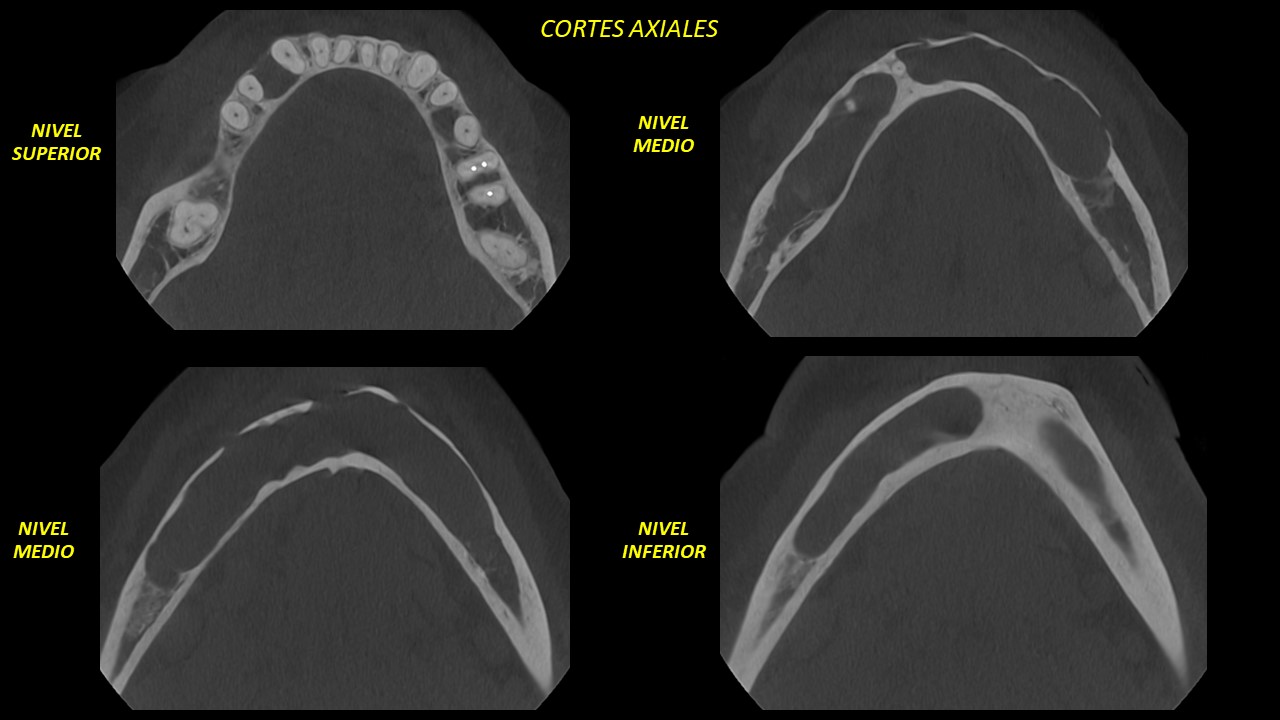

Figura 3

Con la evaluación de la tomografía volumétrica en cortes axiales se evidencia el crecimiento de la lesión desde mesial de pieza 36 hasta mesial de pieza 48, además, el adelgazamiento y erosión de la tabla òsea vestibular y la expansión y adelgazamiento de la tabla òsea lingual. (Figura 3).